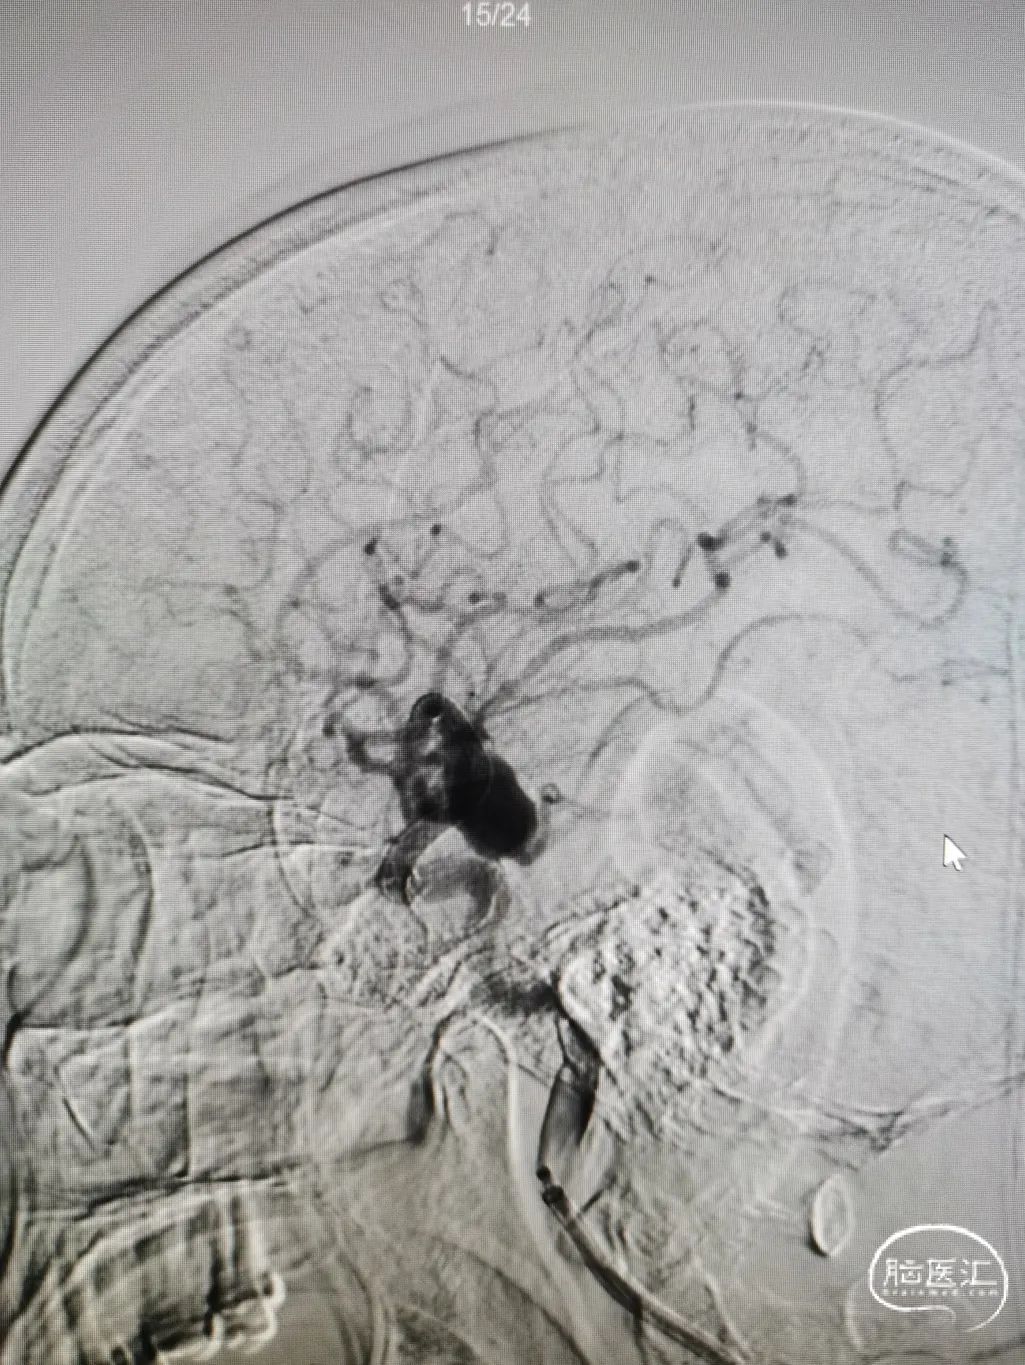

术后造影

术后即可造影可见造影剂滞留,术后顺利复苏,无不适,术后5天出院。

图7

术后三个月返院复查提示血管进一步修复,造影剂滞留明显。

图8